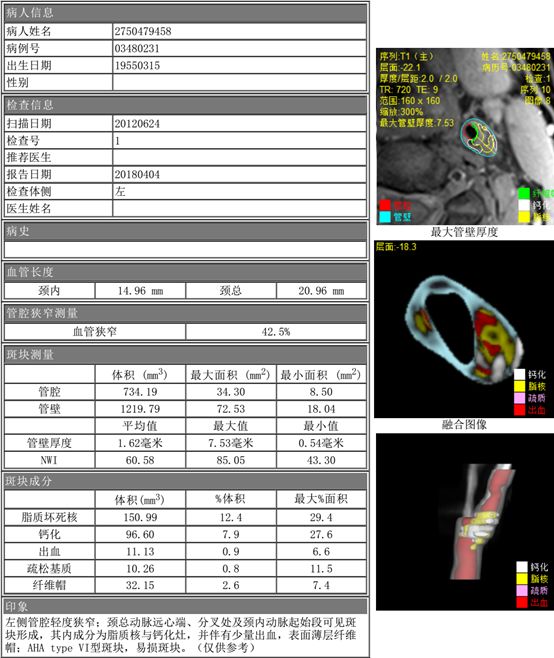

标准化管壁指数(Normal Wall Index,NWI),简单来讲就是:管壁面积/[管腔面积+管壁面积],是一种非常准确且可重复的测量值。 研究表明,正常颈动脉的 NWI 值在 0.4 左右 。 较高的平均动脉 NWI 值 (>0.56) 与颈动脉纤维帽破裂和斑块内出血关联。如图示:

图片来源:https://radiologykey.com/analysis-of-multicontrast-carotid-plaque-mr-imaging/在以上两种情形下,用相对面积反映斑块负荷似乎更方便准确,这也是NWI的独特价值所在。最后的最后,NWI只是磁共振易损斑块诊断检查(MR-VPD,基于MRI-PlaqueView完成)出具的斑块分析报告中的一个指标。充分挖掘分析报告里每个指标的临床应用意义,综合探索不同指标的联合价值,将为颈动脉斑块诊治提供丰富的测量信息,进而为“斑块是不是高危,需不需要治疗,需要什么样的治疗,治疗的效果如何”这些“重要而有争议”的临床决策提供可靠依据。至此,本专题结束,如有其它想继续了解的,欢迎留言!